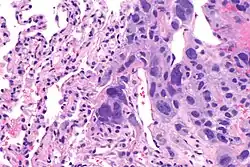

A micrograph showing yolk sac tumour, with smooth external surface and capsule tears

The ovarian yolk sac tumors, also known as endodermal sinus tumors, are accountable for approximately 15.5% of all OGCTs.[8] They have been observed in women particularly in their early ages, and rarely after 40 years of age.[9] The critical pathologic features are a smooth external surface and capsular tears due to their rapid rate of growth. A study consisting of 71 individual cases of ovarian yolk sac tumor provides evidence to the proliferation of the tumor. In one of the cases, the pelvic examination revealed normal activity until a 9 cm and 12 cm sized tumor was discovered 4 weeks later.[9] In another case, a 23 cm tumor was discovered in a pregnant woman who was monitored regularly and had normal findings until oophorectomy became essential.[9] Histologically, these tumors are characterized by mixed solid and cystic components.[1] The mixed solid components are characterized by a soft gray to yellow solid components accompanied with significant hemorrhage and necrosis. The cysts are approximately 2 cm in diameter and populated throughout the tissue which results in giving the neoplasm a ‘honeycombed appearance’.[1]